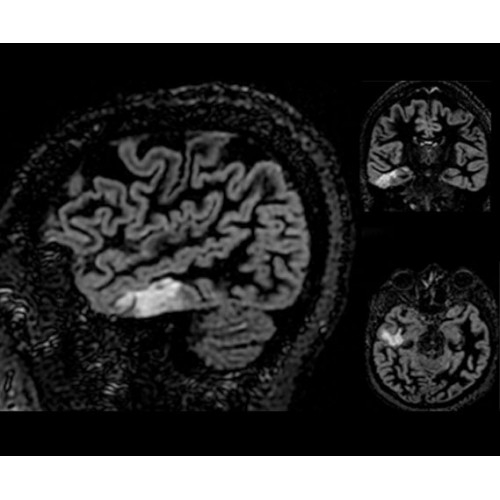

SIGNA PET/MR 3.0T — это гибридная система, в которой совмещаются две принципиально разные технологии — магнитно-резонансную томографию (МРТ) и позитронно-эмиссионную томографию (ПЭТ). Система отличающийся высокой чувствительностью и эффективностью и предназначена для диагностики в области онкологии, неврологии, кардио-васкулярных исследований, исследований воспалительных процессов.

Компания GE Healthcare представляет революционную, полностью интегрированную систему SIGNA PET/MR1, в которой сочетаются времяпролетная технология (TOF) и возможности напряженности магнитного поля 3.0 Тл. Мы поможем вам поднять исследования на более высокий уровень. SIGNA PET/MR позволяет достичь впечатляющей точности и скорости исследований, а благодаря новейшей технологии реконструкции Q.Clear2 качество изображений улучшается в два раза. Кроме того, в систему включен полный набор клинических приложений и гибких катушек для проведения любых видов исследования, открывая для вас возможности визуализации, о которых вы даже не догадывались.

• Q.Clear — в основу технологии легли накопленные знания о том, как минимизировать помехи при реконструкции и получить четкое изображение. При значительном улучшении качества изображения сохраняется точность расчетов. Сочетание технологии TOF и реконструкции Q.Clear — ваш надежный помощник для получения точных и достоверных данных.

• Специальный пакет приложений для измерения и сравнения объемных изображений ЦНС с нормами поможет вам в диагностике нейродегенеративных заболеваний, а дополнительные инструменты визуализации — в постановке точного диагноза с помощью бета-амилоидов и радиоизотопных маркеров ФДГ.